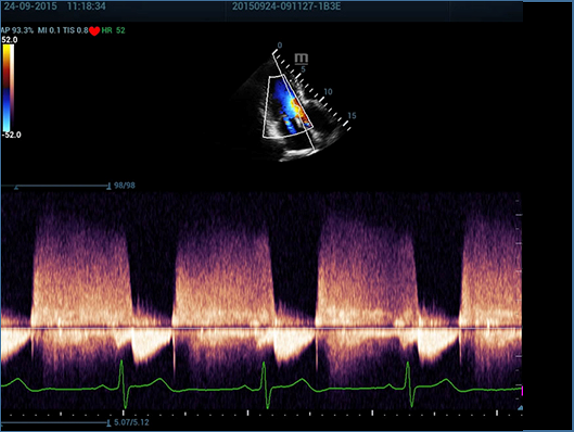

Resona 7, ĂŒstĂŒn dĂŒzeyde g?rĂŒntĂŒ kalitesine ek olarak, vaskĂŒler hemodinamik de?erlendirmesi i?in devrim niteli?indeki V Ak??? ile fetĂŒs CNS tan?lamas? i?in 3 boyutlu veri kĂŒmesinden dĂŒzlem g?rĂŒntĂŒsĂŒ alma konusunda en iyi birime sahip oldu?undan, klinik ara?t?rma yeterliklerini de art?rmaktad?r. En sezgisel, harekete dayal? ?oklu dokunmatik i?letim ile tĂŒm temel klinik ?zellikleri bir araya getiren Resona 7, ultrason yenili?i konusunda ger?ek anlamda yeni dalgalara ?ncĂŒlĂŒk ediyor.